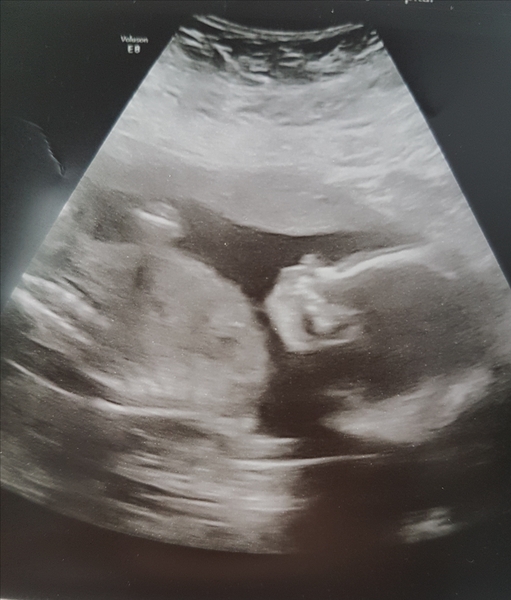

She was sideways enough for the shortest ever bit of time to get this snap, and a few of the other measurements including a good look at her heart, brain and lips! I'm really really thrilled because I haven't had a scan picture like this at all for my whole pregnancy because baby has been vertical!